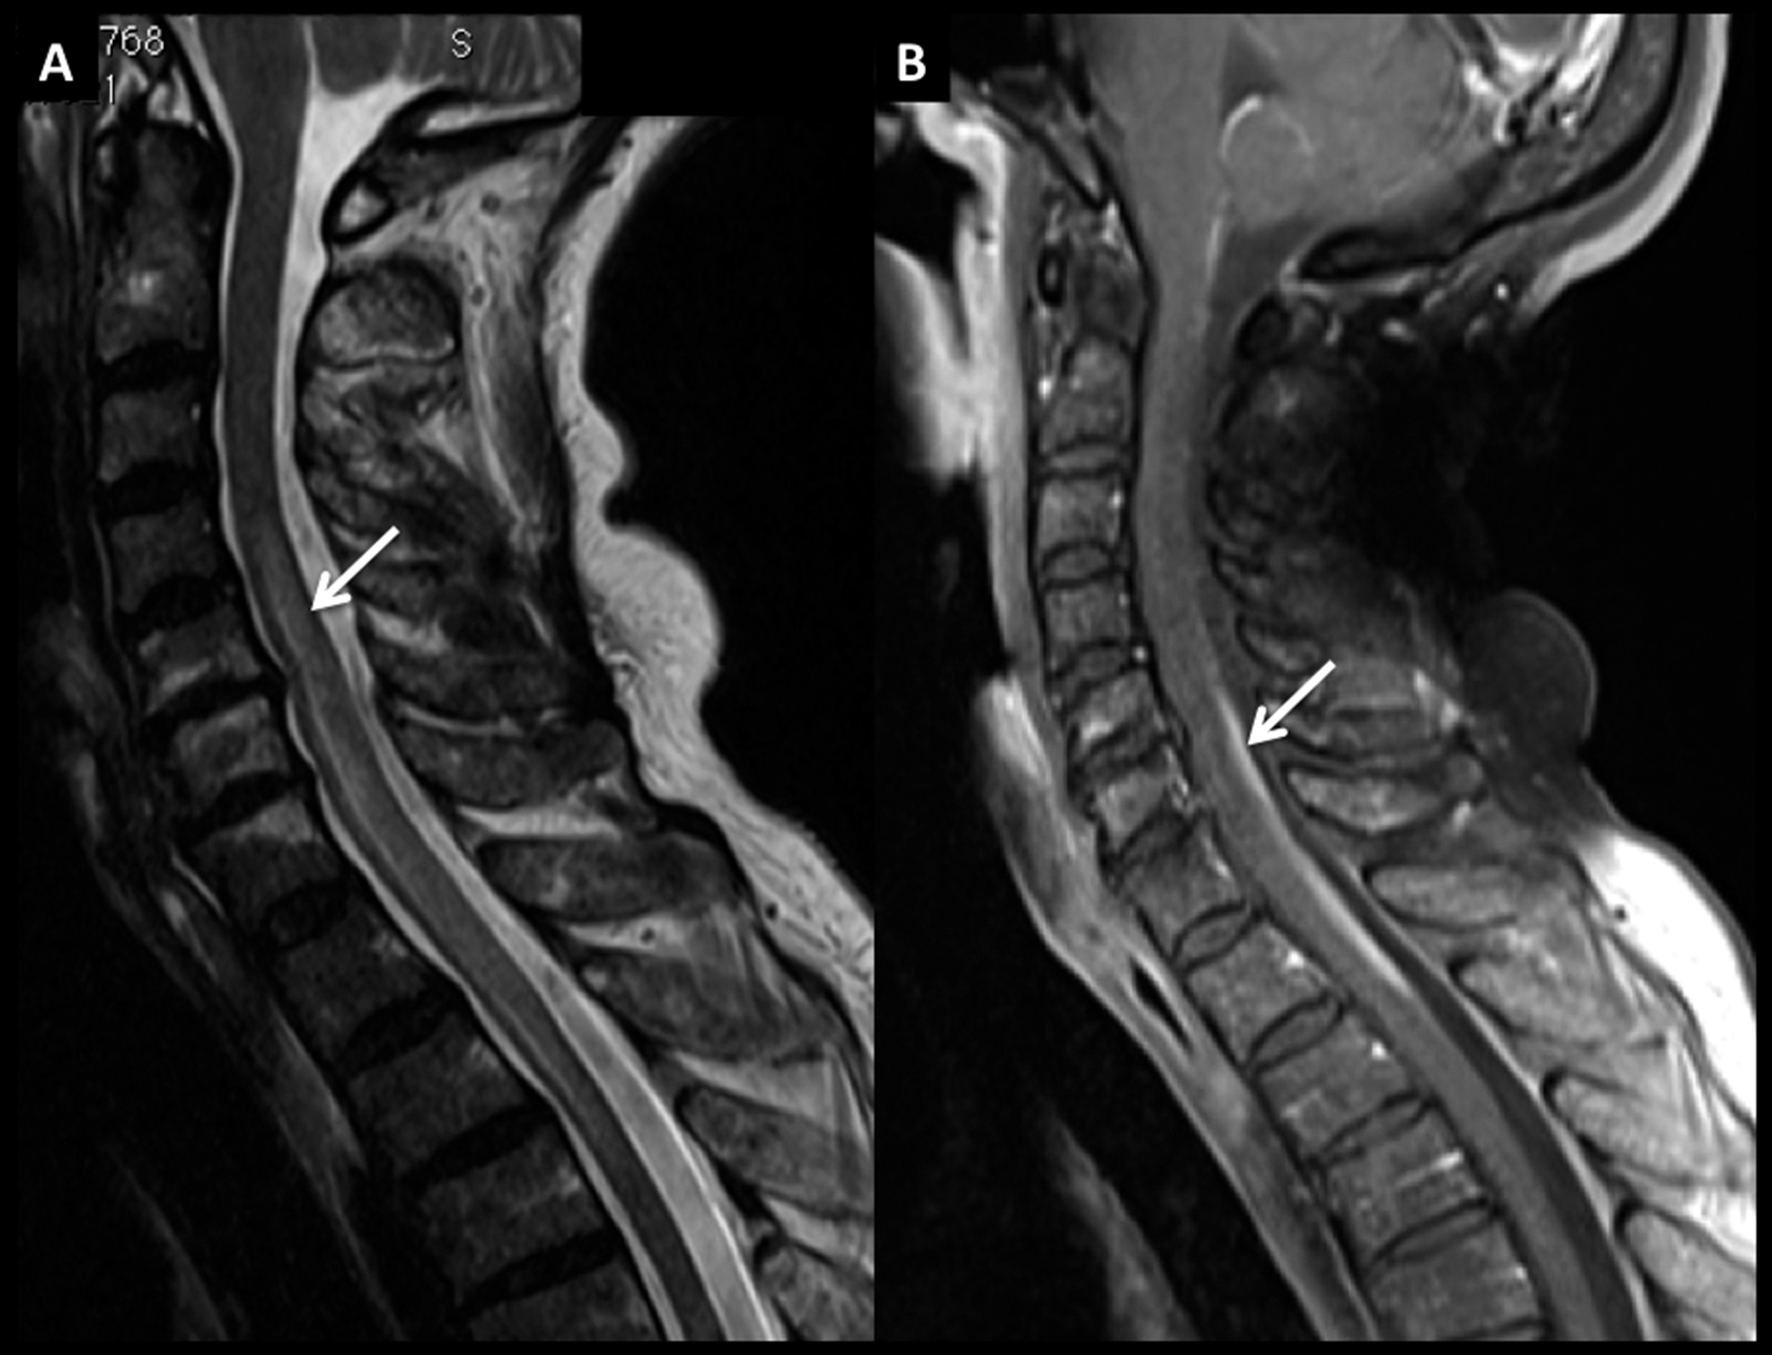

Figura 8

Paciente de 54 años con síndrome medular de instalación progresiva. En RM se identifica lesión medular cervical con ensanchamiento focal de varios segmentos, con alta intensidad de señal en secuencia T2 (A) y realce lineal, intenso, en secuencia T1 post-gadolinio (B).

En secuencia T2 en el plano axial (C) la alteración es heterogénea, centro-medular. Se decidió realizar biopsia de este proceso y el estudio histopatológico confirmó el diagnóstico de linfoma. Luego de la valoración sistémica no se evidenció compromiso asociado en otros territorios por lo que el diagnóstico final fue de LNH primario.